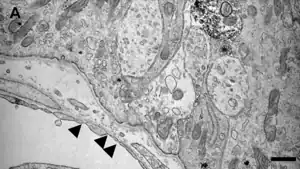

Los NHO presentan capilares fenestrados con poros en su endotelio, de 30-80 nanómetros (nm) de diámetro. Estas fenestraciones se encuentran cubiertas por prolongaciones de las células perivasculares pericitos/tanicitos en los órganos NH sensoriales.[5]

La microscopía electrónica ha demostrado que los CVO-Sn, presentan poros en el endotelio de 30 a 80 nanómetros (nm) de diámetro. Estas fenestraciones se encuentran cubiertas por prolongaciones de las células perivasculares similares a pericitos/tanicitos.[5]